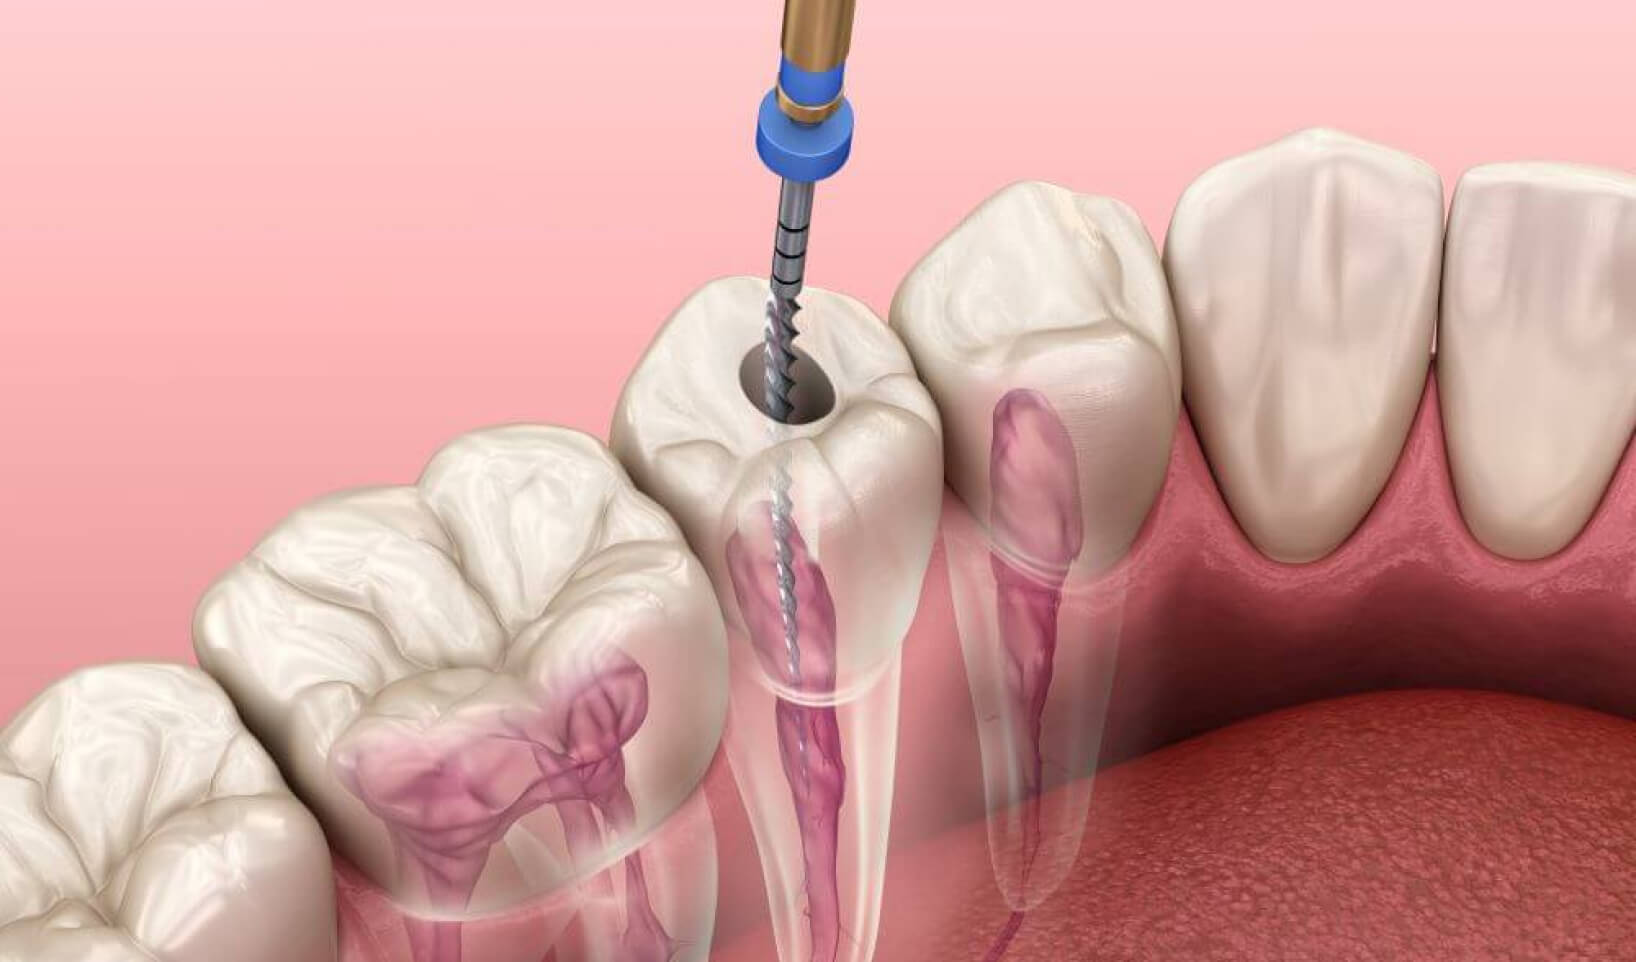

When infection is suspected, a radiograph or Cone Beam CT (CBCT) scan is taken to verify this and, if infection is confirmed, an access hole is created into the tooth, the dentist usually viewing the infected area through a high-magnification loupe or endodontic operating microscope. This will help your consultant to locate all of the root canals whilst keeping tooth removal to an absolute minimum.

The infected nerve tissue and related debris is removed using specialist files and rotary instruments, as well as sonic and ultrasonic powered irrigation. Once the tooth has been thoroughly cleansed it is filled and sealed temporarily to allow it to heal. The temporary seal is then removed and a crown is added.